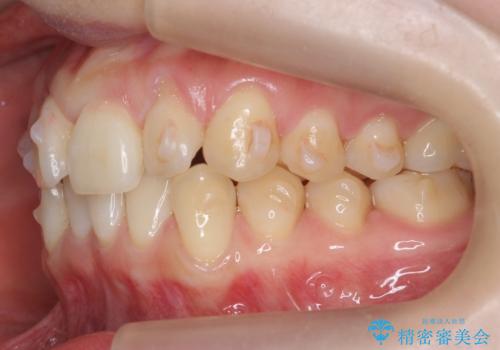

前歯がねじれている 奥歯を後ろに下げて歯を抜かずに並べました

- 前歯のねじれを主訴に来院。

前から2番目の歯がねじれて下の歯の内側に入っていました。

また、奥歯のかみ合わせが上の奥歯が若干前に並んでおり、それで前歯が入りきらずにねじれていました。

歯を抜かずに奥歯を後ろに下げてマウスピースで矯正しています。

上の奥歯を後ろに下げて前歯のねじれを治すスペースを確保しました。

奥歯を後ろに下げるために、矯正用インプラントを使用しています。